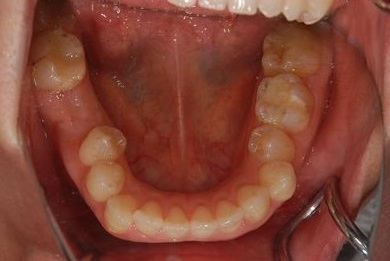

| 主訴 | 前歯と奥歯の虫歯と、前歯の歯並び(でこぼこ)・歯の形(小さくとがった形が気になる)を治したい。 | ||||||||||||||||||||||||||||||||

| 治療方針 | 上顎前歯1歯抜歯し、オールセラミックブリッジ、クラウン、ラミネートベニアにて審美的回復を行う。 | ||||||||||||||||||||||||||||||||

| 治療内容 | オールセラミッククラウン2本、ジルコニアフレームオールセラミックブリッジ3本、オールセラミックラミネートベニア2本、骨造成(欠損部) | ||||||||||||||||||||||||||||||||